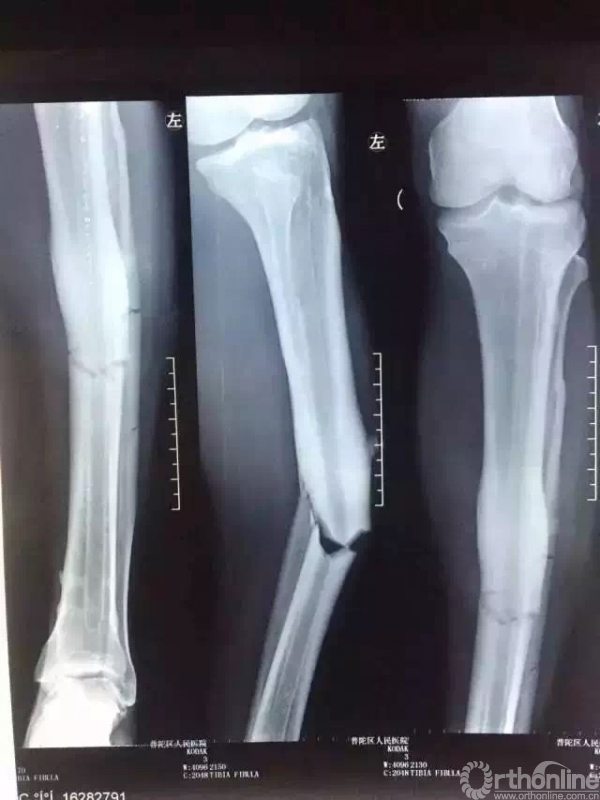

2016年7月17日,球员登巴巴在中超比赛拼抢中遭遇重伤,被诊断为左胫腓骨中段骨折。

急诊X光片

登巴·巴受伤当日,复旦大学附属华山医院及普陀区人民医院领导高度重视,华山医院夏军教授、陈文钧教授连夜赶往上海普陀区人民医院,与骨科主任陈舰共同完成全麻下手法复位,石膏固定。复位后X光片示效果满意,随后进行镇痛、消肿等对症治疗。

复位后x光片